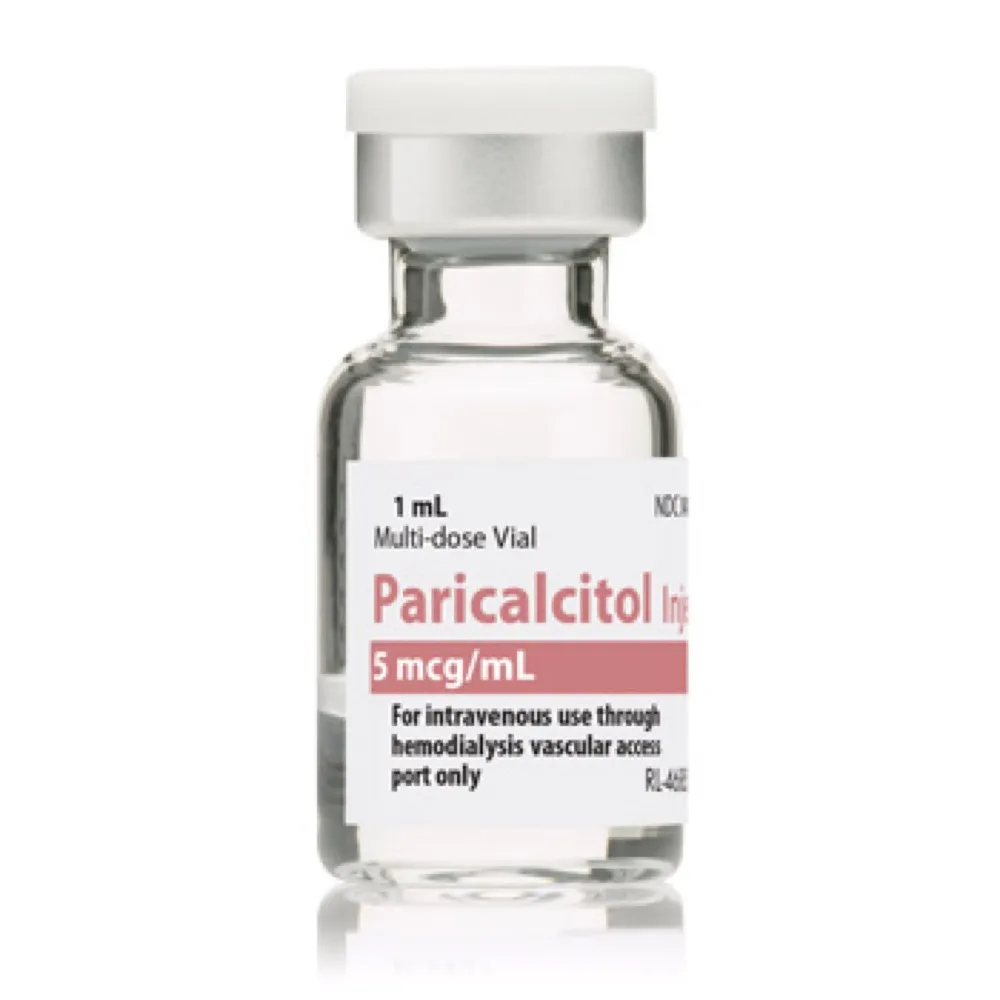

Prurido na DRC: passo a passo prático que funciona

Prurido na DRC: passo a passo prático que funciona